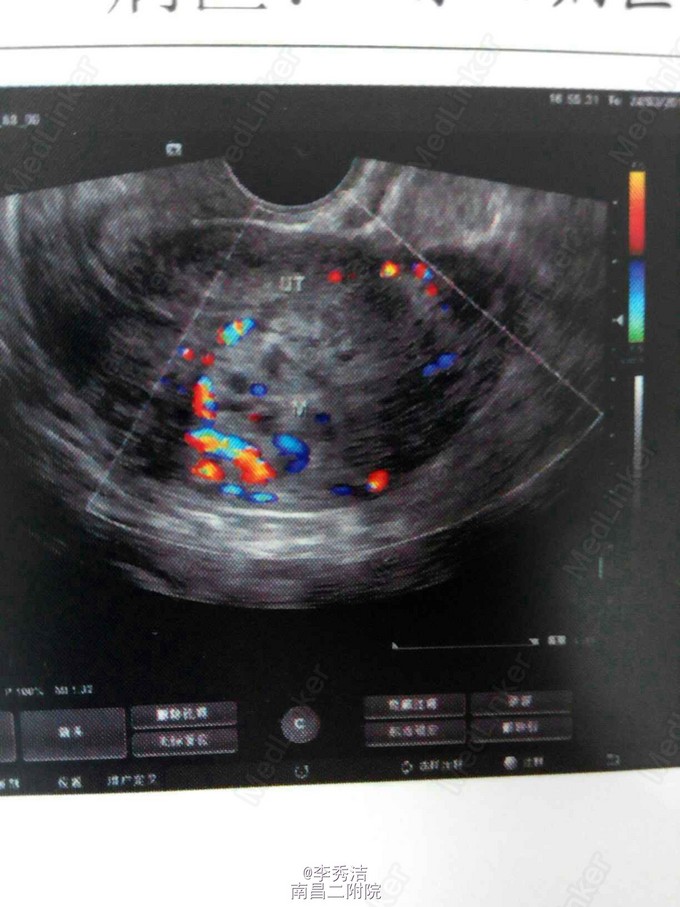

患者女,24岁,因“产后阴道不规则出血4月,发现妊娠滋养细胞肿瘤5天”入院。 患者于2014年12月11日足月自阴道分娩一胎儿(死胎)。后因阴道流血不尽,于2015年2月4日至当地医院清宫,未送病检。于2015年3月7日阴道血未干净至外地医院行第二次清宫,送病理报告示:(宫腔内刮出物)血块中见显著增生滋养叶细胞,核异形明显,考虑滋养叶细胞肿瘤,另见少量蜕膜组织。自诉6天前因阴道出血量多,明显多于月经量,至当地医院行阴道壁修补术。现无阴道流血,稍感下腹部隐痛,无头痛、发热等不适。门诊拟“阴道流血原因待查:滋养叶细胞肿瘤?”收入院。患者自发病以来,精神食欲睡眠可,大小便正常,体重无明显变化,否认高血压、糖尿病等慢性病史;否认传染病史;无食物药物过敏史,无手术及外伤史。平素月经规律,4~6天/33天,末次月经2014年3月26日,量中活动,暗红,有痛经,无血块。已婚,妊娠2,足月顺产2(1为死胎),未避孕。 查体:生命体征平稳,心肺听诊未及异常,腹平软,无压痛及反跳痛。妇检:外阴:已婚已产式;阴道:畅软,内见少量暗红色血液,前壁见两针丝线缝合;宫颈:光滑;宫体:平后位,超鸭蛋大小,质中、活动、无压痛;双附件未及异常。 辅助检查:2015年3月19日外院病理报告示:(宫腔内刮出物)血块中见显著增生滋养叶细胞,核异形明显,考虑滋养叶细胞肿瘤,另见少量蜕膜组织。血HCG209675mIU/ml。胸部CT示:肺部转移病灶。我院彩超示:子宫内混合回声团块,考虑滋养细胞肿瘤。 诊断:绒毛膜癌III期 诊疗计划:考虑患者为高危,使用联合化学药物治疗,5-FU+国产放线菌素D(更生霉素 KSM)。使用方法:5-FU 26~28mg/(Kg. d)+KSM6ug/(Kg. d)。静脉注射8天,每周检测血HCG水平一次。间隔13天进行第二次化疗。停药指证:HCG连续三次阴性后,继续给予三个疗程化疗。